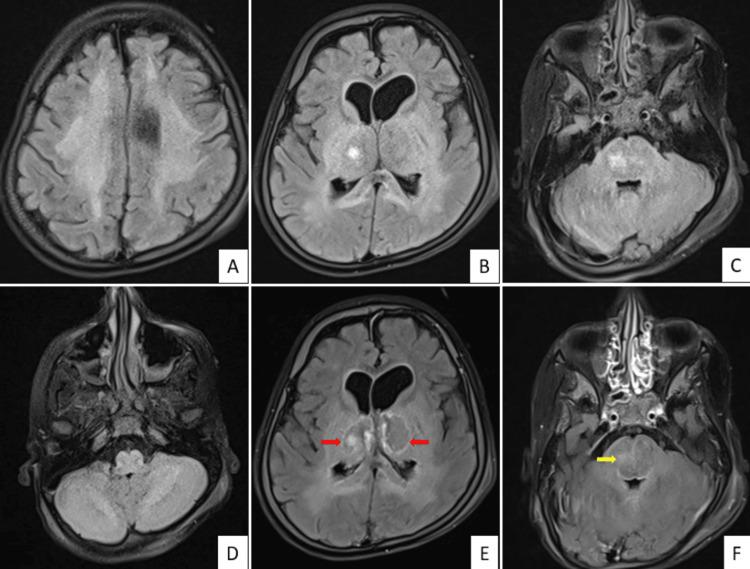

Acute necrotizing encephalopathy of childhood (ANEC) is a severe neurological disorder characterized by rapid-onset encephalopathy, often associated with viral infections. Acute necrotizing encephalopathy of childhood is associated with a very high mortality rate, and survivors may face long-term neurological sequelae. Acute necrotizing encephalopathy of childhood needs to be differentiated from its closest differential diagnosis, acute disseminated encephalomyelitis (ADEM). Most of the patients with ADEM recover, with a few of them having residual neurological deficits. We present a case of an eight-year-old boy with an acute history of fever, febrile seizures, and drowsiness. Magnetic resonance imaging revealed a symmetric tricolor appearance of bilateral thalamic lesions, characteristic of ANEC.

儿童急性坏死性脑病(ANEC)是一种严重的神经系统疾病,其特征为快速起病的脑病,常与病毒感染相关。儿童急性坏死性脑病的死亡率非常高,幸存者可能面临长期神经后遗症。儿童急性坏死性脑病需要与其最相近的鉴别诊断——急性播散性脑脊髓炎(ADEM)相区分。大多数ADEM患者可康复,少数患者有残留神经功能缺损。我们报告一例8岁男孩,有发热、热性惊厥及嗜睡的急性病史。磁共振成像显示双侧丘脑病变呈对称的三色外观,这是ANEC的特征表现。